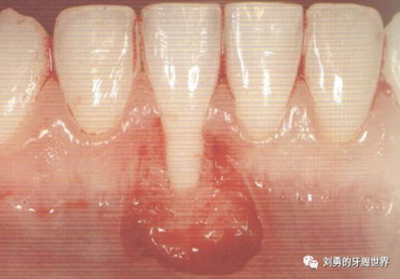

上圖中,種植體唇側(cè)缺乏附著齦,從上腭取瓣,常規(guī)做法:取長而寬的齦瓣,這樣供區(qū)面積大,術(shù)后疼痛重。

為了減少痛感,從雙側(cè)上腭取多條長而窄的齦瓣進(jìn)行移植,這樣每個供區(qū)的傷口都比較窄,可以減少術(shù)后的痛感。

可見右上前牙植體頰側(cè)無附著齦

為了減少取瓣大小,從上腭取厚一點(diǎn)的齦瓣,然后用刀片平行于表皮表面將齦瓣片切成兩個厚度一致的齦瓣,然后進(jìn)行移植,這樣切成的兩個齦瓣一個有表皮,一個沒有表皮是單純的結(jié)締組織。如此的片切可以使齦瓣變成雙倍的大小使用,減少了供區(qū)的取瓣面積。